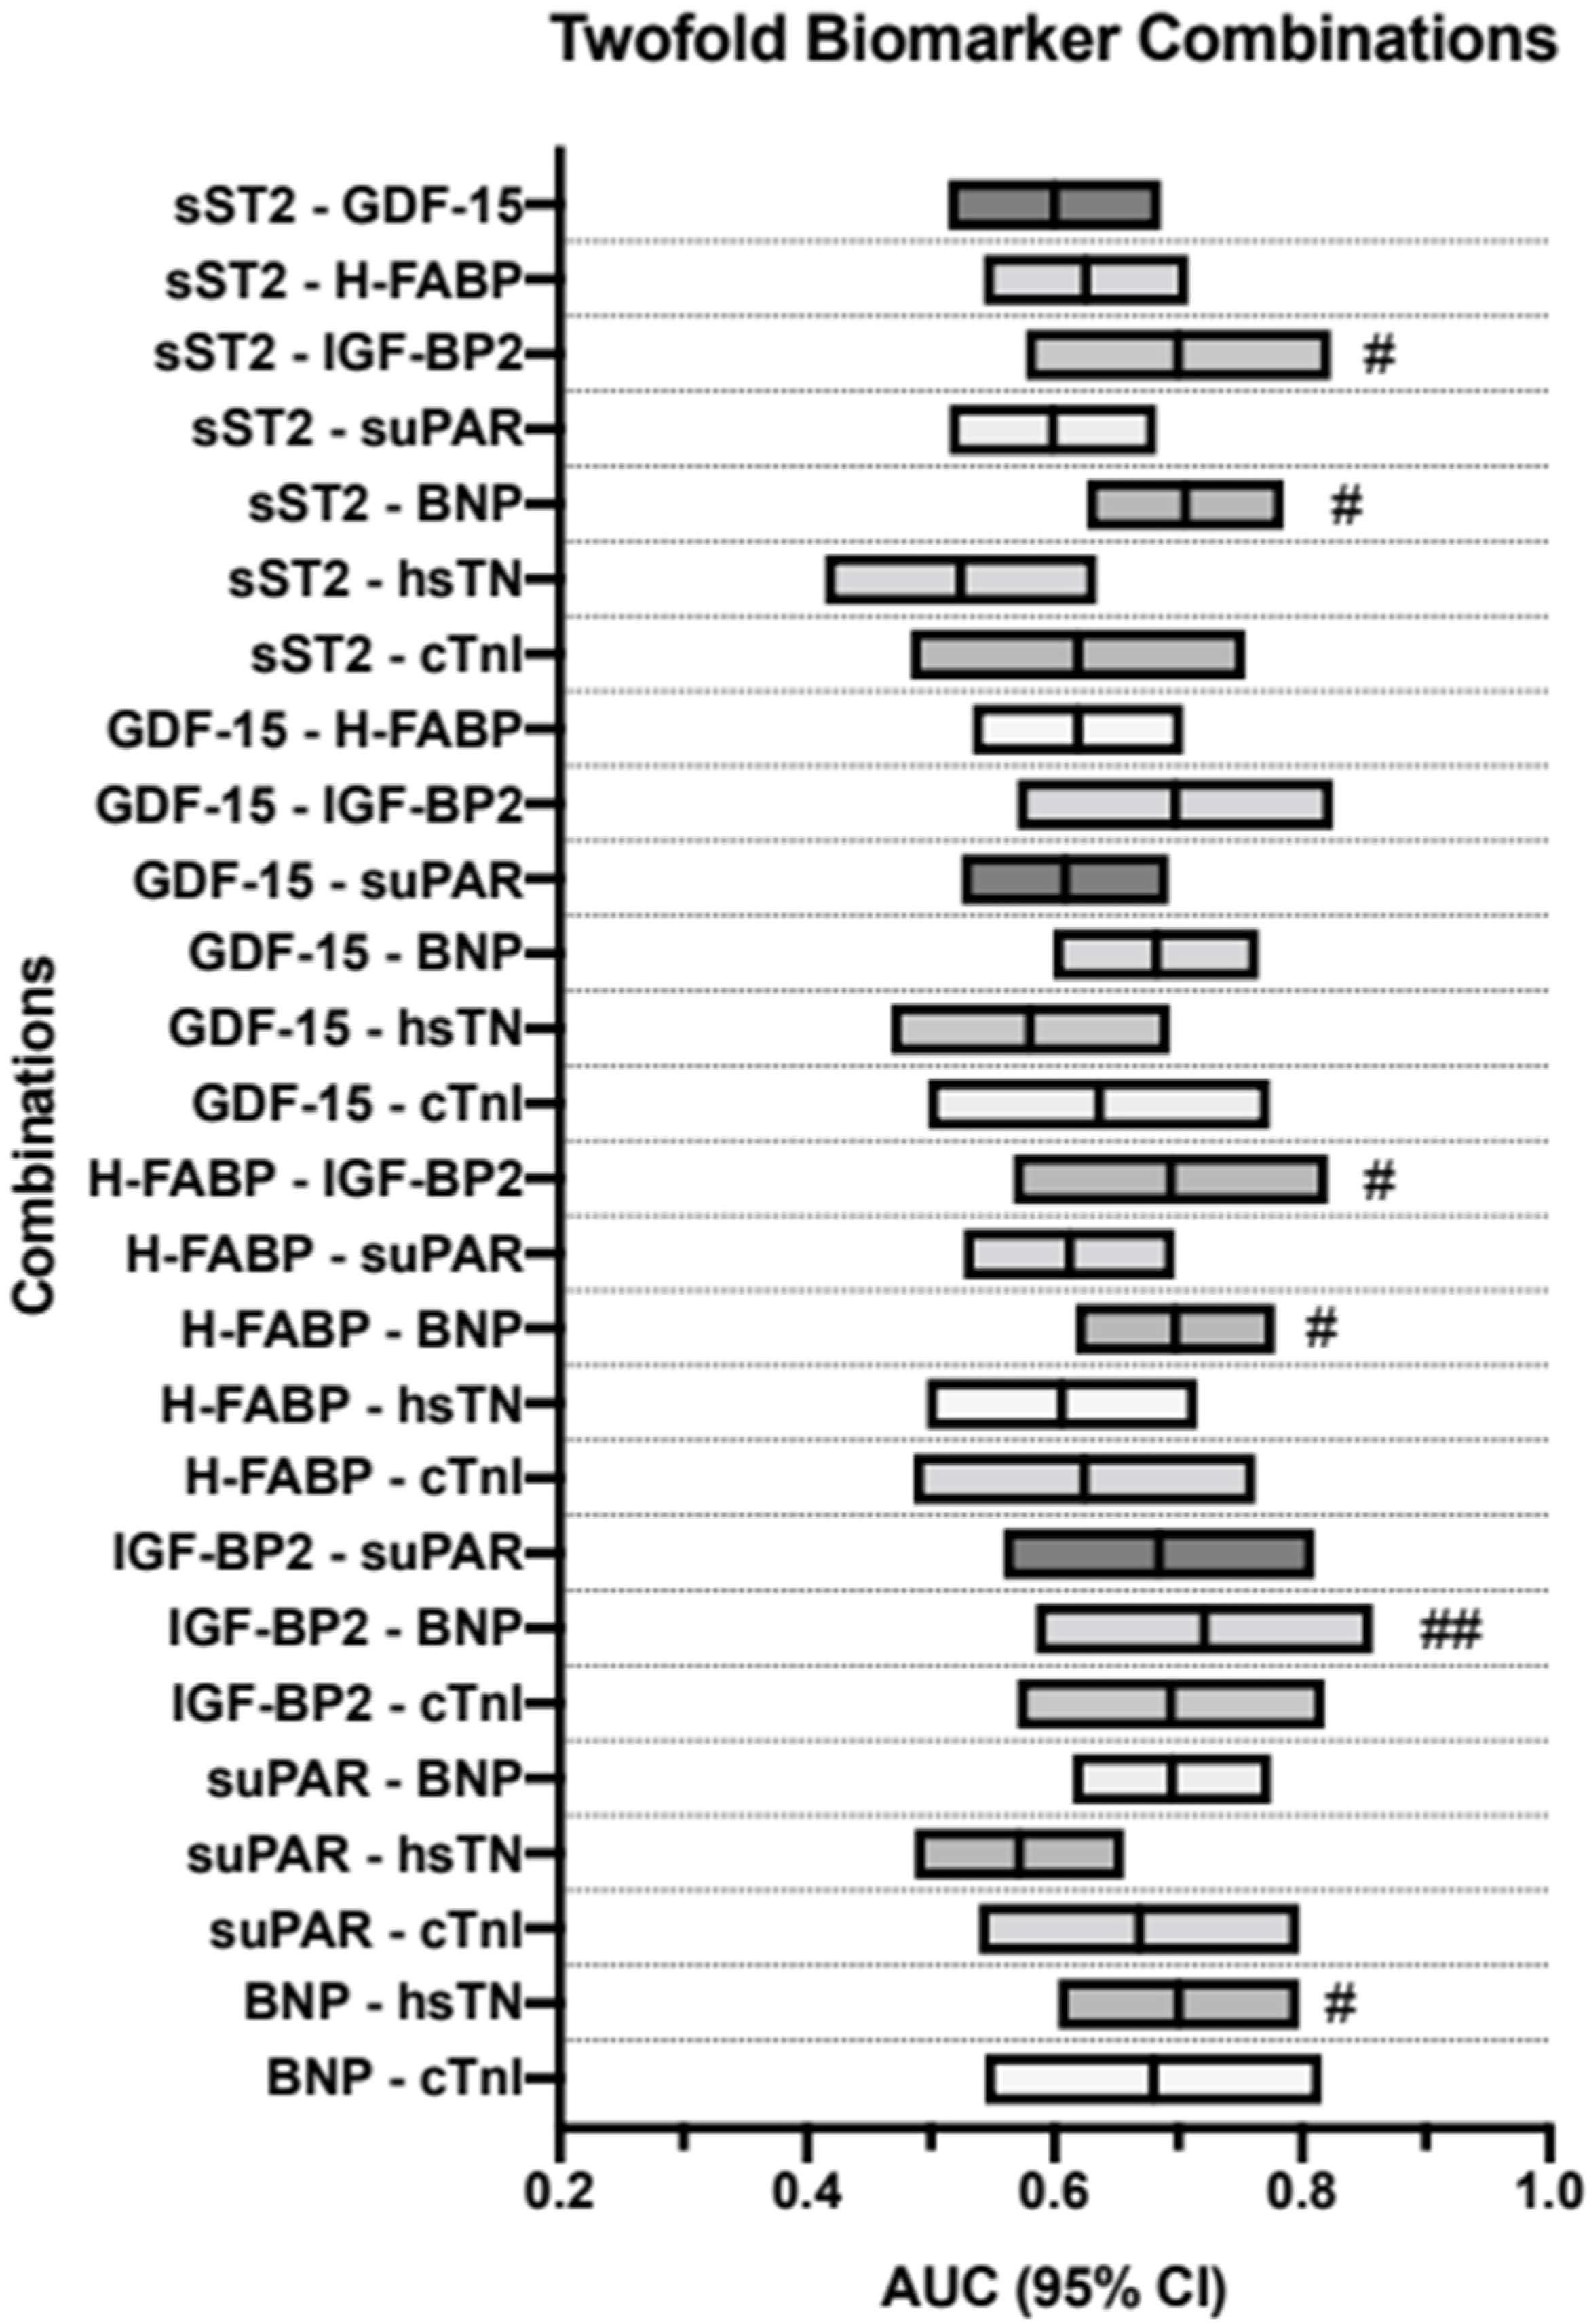

3.8. AUROC Results—PA/BSA vs. Triple-Biomarker Combinations

| Values | Prediction | AUC | 95%CI | p-Value | Sensitivity | Specificity | Youden Index |

|---|---|---|---|---|---|---|---|

| sST2—GDF-15 | PA/BSA ≥ 16.6 mm/m2 | 0.600 | 0.514–0.686 | 0.022 | 0.34 | 0.88 | 0.22 |

| sST2—H-FABP | PA/BSA ≥ 16.6 mm/m2 | 0.625 | 0.543–0.708 | 0.004 | 0.67 | 0.56 | 0.23 |

| sST2—IGF-BP2 | PA/BSA ≥ 16.6 mm/m2 | 0.700 | 0.577–0.823 | 0.004 | 0.53 | 0.81 | 0.35 |

| sST2—suPAR | PA/BSA ≥ 16.6 mm/m2 | 0.599 | 0.515–0.682 | 0.220 | 0.30 | 0.93 | 0.22 |

| sST2—BNP | PA/BSA ≥ 16.6 mm/m2 | 0.706 | 0.626–0.785 | < 0.001 | 0.71 | 0.67 | 0.38 |

| sST2—hsTN | PA/BSA ≥ 16.6 mm/m2 | 0.524 | 0.415–0.634 | 0.056 | 0.77 | 0.38 | 0.14 |

| sST2—cTnI | PA/BSA ≥ 16.6 mm/m2 | 0.619 | 0.484–0.754 | 0.092 | 0.59 | 0.66 | 0.25 |

| GDF-15—H-FABP | PA/BSA ≥ 16.6 mm/m2 | 0.619 | 0.534–0.704 | 0.006 | 0.67 | 0.62 | 0.29 |

| GDF-15—IGF-BP2 | PA/BSA ≥ 16.6 mm/m2 | 0.698 | 0.570–0.825 | 0.005 | 0.64 | 0.72 | 0.36 |

| GDF-15—suPAR | PA/BSA ≥ 16.6 mm/m2 | 0.609 | 0.525–0.692 | 0.013 | 0.49 | 0.74 | 0.22 |

| GDF-15—BNP | PA/BSA ≥ 16.6 mm/m2 | 0.682 | 0.599–0.765 | <0.001 | 0.76 | 0.58 | 0.34 |

| GDF-15—hsTN | PA/BSA ≥ 16.6 mm/m2 | 0.580 | 0.468–0.693 | 0.153 | 0.51 | 0.74 | 0.25 |

| GDF-15—cTnI | PA/BSA ≥ 16.6 mm/m2 | 0.636 | 0.498–0.774 | 0.059 | 0.48 | 0.83 | 0.31 |

| H-FABP—IGF-BP2 | PA/BSA ≥ 16.6 mm/m2 | 0.694 | 0.567–0.821 | 0.006 | 0.46 | 0.88 | 0.35 |

| H-FABP—suPAR | PA/BSA ≥ 16.6 mm/m2 | 0.612 | 0.527–0.697 | 0.010 | 0.51 | 0.74 | 0.25 |

| H-FABP—BNP | PA/BSA ≥ 16.6 mm/m2 | 0.698 | 0.617–0.778 | <0.001 | 0.78 | 0.62 | 0.39 |

| H-FABP—hsTN | PA/BSA ≥ 16.6 mm/m2 | 0.606 | 0.497–0.715 | 0.056 | 0.45 | 0.77 | 0.22 |

| H-FABP—cTnI | PA/BSA ≥ 16.6 mm/m2 | 0.624 | 0.486–0.762 | 0.086 | 0.59 | 0.68 | 0.28 |

| IGF-BP2—suPAR | PA/BSA ≥ 16.6 mm/m2 | 0.684 | 0.559–0.810 | 0.008 | 0.43 | 0.88 | 0.32 |

| IGF-BP2—BNP | PA/BSA ≥ 16.6 mm/m2 | 0.721 | 0.585–0.857 | 0.004 | 0.68 | 0.73 | 0.41 |

| IGF-BP2—cTnI | PA/BSA ≥ 16.6 mm/m2 | 0.694 | 0.570–0.818 | 0.005 | 0.63 | 0.70 | 0.33 |

| suPAR—BNP | PA/BSA ≥ 16.6 mm/m2 | 0.695 | 0.615–0.775 | <0.001 | 0.47 | 0.84 | 0.31 |

| suPAR—hsTN | PA/BSA ≥ 16.6 mm/m2 | 0.572 | 0.487–0.656 | 0.097 | 0.83 | 0.31 | 0.14 |

| suPAR—cTnI | PA/BSA ≥ 16.6 mm/m2 | 0.669 | 0.539–0.798 | 0.017 | 0.69 | 0.63 | 0.32 |

| BNP—hsTN | PA/BSA ≥ 16.6 mm/m2 | 0.700 | 0.603–0.798 | <0.001 | 0.54 | 0.82 | 0.36 |

| BNP—cTnI | PA/BSA ≥ 16.6 mm/m2 | 0.680 | 0.544–0.816 | 0.018 | 0.89 | 0.44 | 0.33 |